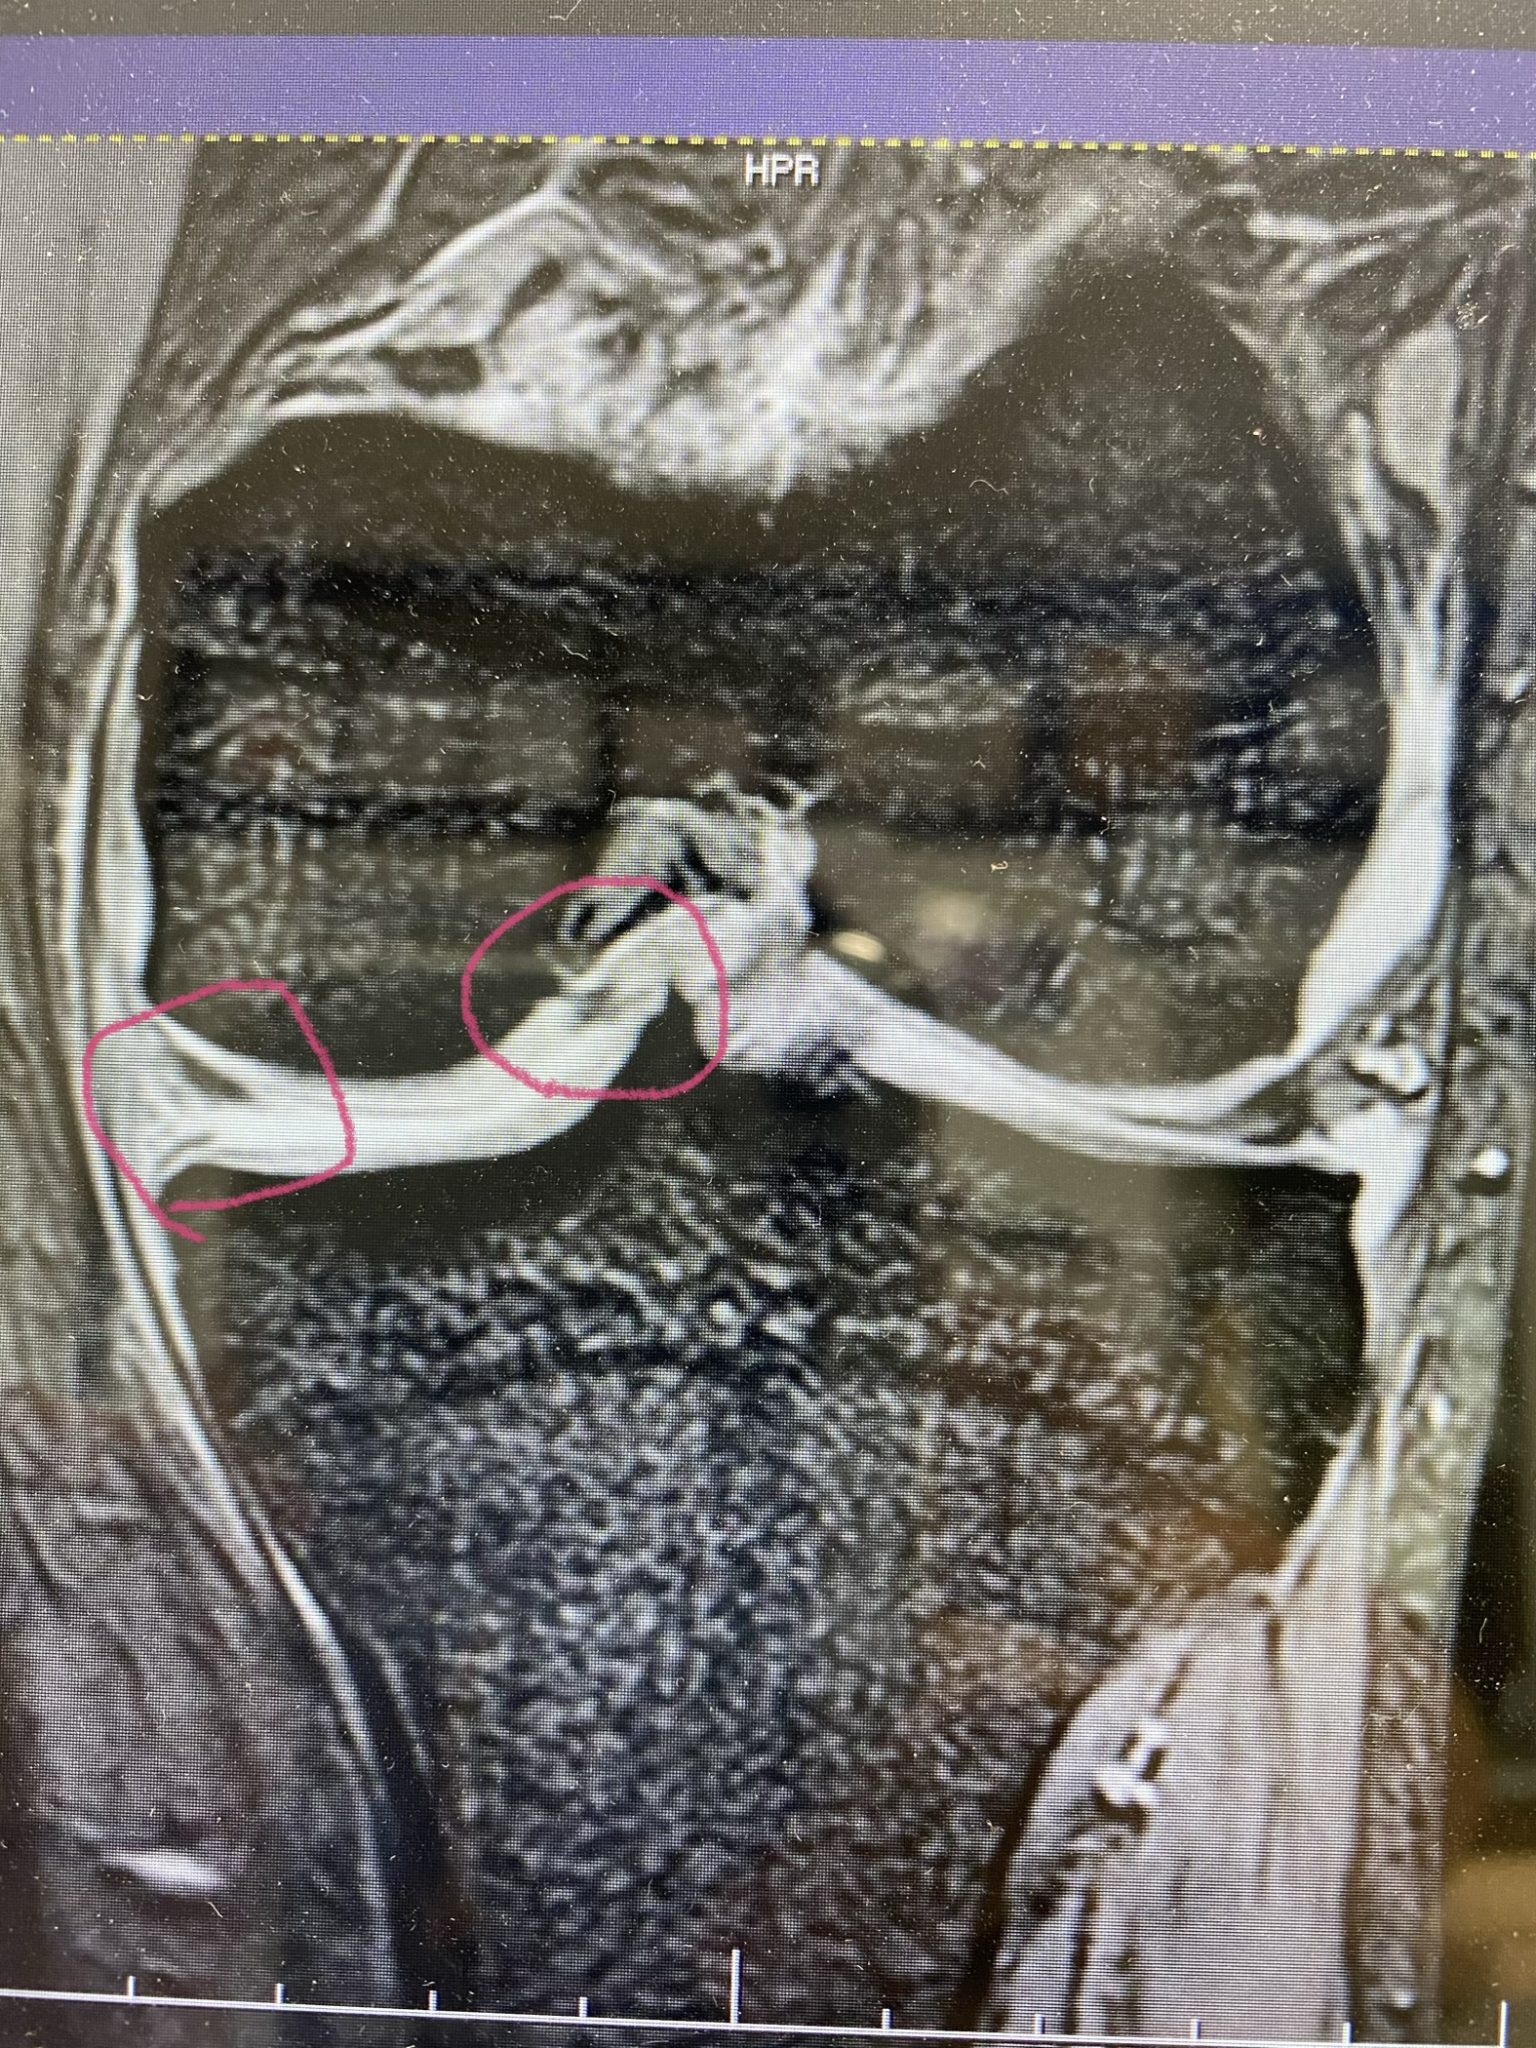

診断結果は「左膝内側の半月板が断裂しています。そして断裂した部分が吹き飛んで膝の真ん中辺りに挟まってますね。痛くてて曲がらないでしょう。手術しましょう!」

歩けるようになり階段の昇り降りも出来るようになりましたが、断裂したのが挟まっているせいか、

ロッキングという現象でまだ完全な曲げ伸ばしはできていませんが普通にしてる分には痛みもありません☆